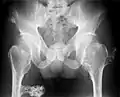

múltiples osteocondromas en la pelvis